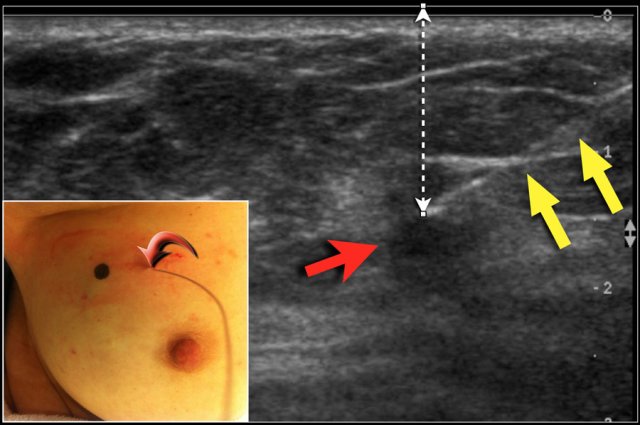

Wire localisation

DCIS and many small tumors are not palpable. In these cases, the radiologist places a hook wire in the area that needs to be removed.

The wire is placed within the tumor or the area of DCIS, either US-guided or stereotactically.

With US, the position of the tumor is marked on the skin, while the patient holds her arm in the same position as during surgery. The exact depth of the tumor beneath the skin is also noted.

The figure shows the tract of the wire (yellow arrows) towards the tumor (red arrow). Notice the black dot on the skin to mark the exact position of the tumor.

The curved arrow indicates the entrance of the wire into the breast.